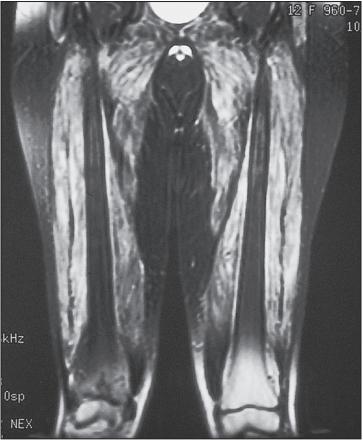

肌肉活检的光镜检查

但是如何做肌肉活检?仅仅根据症状就行肌肉活检是不妥的。尤其采用医生体检按压肌肉寻找肌肉活检部位。这是因为临床按压本身可能误导肌肉活检结果。为此,予以磁共振(MRI)检查肌肉是必要的。因为MRI对早期肌组织病变和钙质沉着敏感。采用T2加权和压脂序列可以清楚显示病变范围,提高肌电图及肌活检的阳性率。虽然「皮肌炎和多发性肌炎」临床表现为对称性近端肌肉受累,但MRI可以显现不均匀和不对称性。MRI阳性改变在一些血清肌酶正常的「皮肌炎和多发性肌炎」中亦不少见。因此, 可用于评估疾病活动性、 累及损害和对治疗的反应。

一儿童皮肌炎的MRI压脂图像显示,关注白色提示肌肉炎症